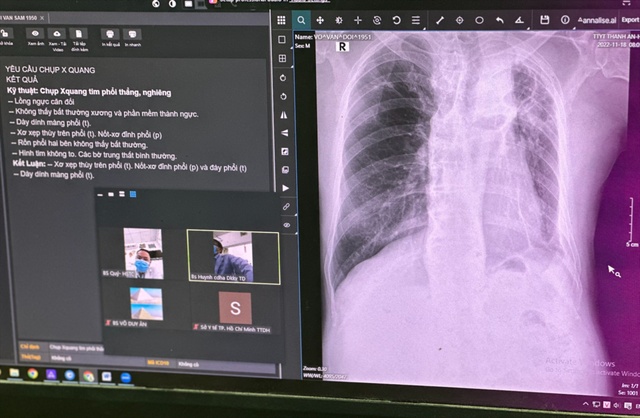

Sở Y tế TP.HCM vừa khởi động chương trình Nâng cao năng lực y tế xã đảo Thạnh An. Lần đầu tiên Trạm Y tế Thạnh An đưa vào vận hành máy X-quang tại giường hiện đại có tích hợp trí tuệ nhân tạo (AI) và hệ thống PACS (lưu trữ, truyền hình ảnh).

Để khám và kiểm tra sức khoẻ của một người bệnh ho ra máu, chỉ vài động tác chạm tay lên màn hình của máy X-quang, BS. Tỷ đã tự tin đọc các thương tổn trên phim X-quang là xẹp phân thuỳ phổi P, dày màng phổi và tràn dịch màng phổi T.

Nhờ ứng dụng AI được tích hợp trên máy X-quang kỹ thuật số và kết nối hệ thống PACs, các thương tổn trên X- quang phổi nhanh chóng được liệt kê trên màn hình; đồng thời, các hình ảnh X-quang phổi vừa chụp được dễ dàng chuyển đi để xin ý kiến tư vấn của các bác sĩ chuyên khoa tại Bệnh viện Đa khoa khu vực Thủ Đức.

Chưa tới 15 phút, sau khi xin ý kiến của các bác sĩ tuyến trên, bác sĩ trẻ tại trạm y tế này đã có được chẩn đoán chính xác và kế hoạch điều trị rõ ràng cho người bệnh.

Đây là trạm y tế đầu tiên của cả nước đã ứng dụng thành công trí tuệ nhân tạo trong chẩn đoán hình ảnh X-quang phổi, thông qua hệ thống PACS và ứng dụng telemedicine.